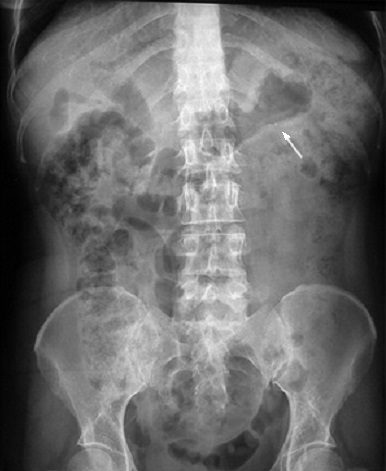

ASP en face couche :

L'ombre du foie est en vue a la region sous

phrenique droit . Image de gaz dans colon ascendant

, colon transverse et de l'estomac se voyait si net

. La diference du cliche ASP de face e st aspect

arondie du |

Image aerique de l'estomac en

se voyait tres claire . Cliche ÁP de face en

decubilus dorsale |

Image typique hydro-aerique

de l'estomac se voyait net su r cliche de face

debout . Image radiologique ÁP de face debout |